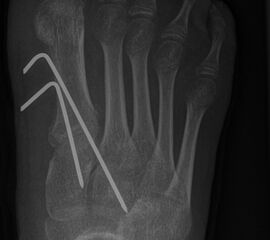

Werden komplette Osteotomien an den Zehen durchgeführt, fädeln wir die Osteotomien mit einem 1.2 oder 1.4 mm Kirschner-Draht auf, damit die einzelnen Fragmente nicht verkippen (Abb. 22).

Abb. 22 a-d: Präoperative Klauenzehen beim Jugendlichen in zwei Ansichten (a-b) und postoperative Auffädelung mit Kirschner-Drähten linker und rechter Fuß (c-d).

Nach unserer Erfahrung können komplette Osteotomien nicht so gut in einem Tapeverband stabil gehalten werden. Im Fall von Derotationen kombinieren wir einen Draht mit externen Tapezügeln, um das Ergebnis zu sichern. Die Drähte werden 2-3 Wochen belassen und anschließend in der Sprechstunde gezogen. Anschließend wird die Zehe noch 2 weitere Wochen mit Tape gezügelt (Abb. 23).